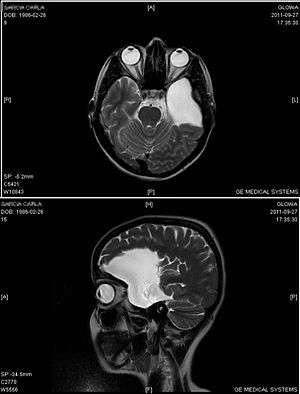

An MRI of a 25-year-old woman with left frontotemporal arachnoid cyst. | |